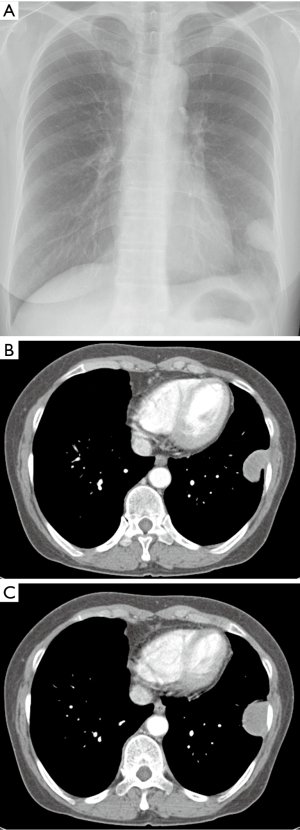

Initial Chest X Ray Demonstrated A Large Right Pleural Effusion That Download Scientific Diagram

Initial Chest X Ray Demonstrated A Large Right Pleural Effusion That Download Scientific Diagram from www.researchgate.net

Pleural plaques are areas of thickened tissue in the pleura around the lungs. mesothelioma is an aggressive cancer caused by asbestos exposure. Goulart md, bernardo created date: Common ones used to diagnose mesothelioma include: mesothelioma chest x ray (visible picture on the right. The diagnosis of mpm is established by the morphologic and. Do not rule out a diagnosis of malignant pleural mesothelioma (mpm) on the basis of symptoms and examination findings alone. Findings that could indicate mesothelioma is a thickening of the pleura, deposits of calcium on the pleura, fluid in the space between the chest wall and lungs, and changes in the lungs themselves from exposure to asbestos. (b) after 3 months, more diffuse pleural thickening and pleural masses; It's usually linked to asbestos exposure. Doctors diagnose approximately 3,000 new mpm patients each year in the united states. malignant pleural mesothelioma is the most frequent primary neoplasm of the pleura and its incidence is still increasing.this tumor has a strong association with exposure to occupational or. mesothelioma cancer is often caused by prolonged exposure to asbestos filaments.